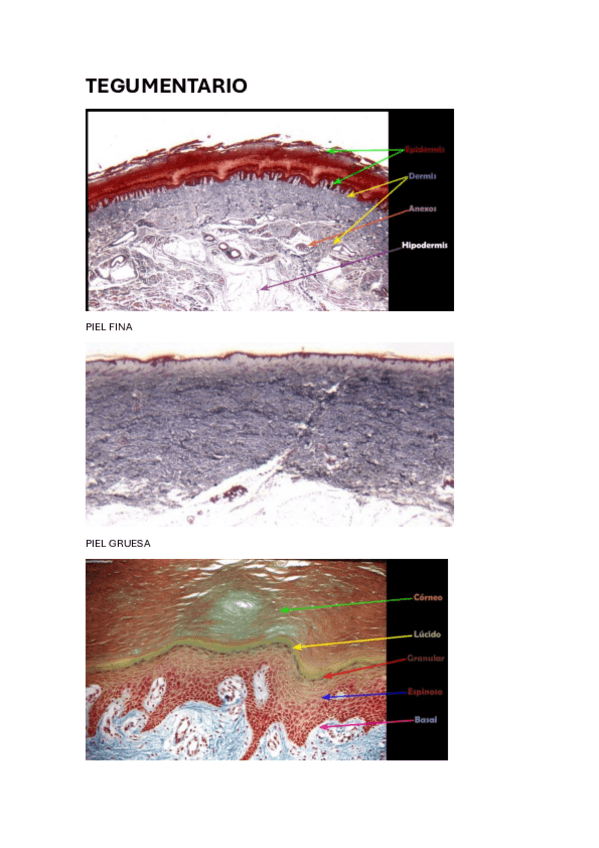

PRÁCTICAS HISTOLOGIA

Todas las practicas de histologia resueltas y con imágenes

He publicado nuevos apuntes de 1º Histología Médica: HISTOLOGIA-T1-TEGUMENTARIO.pdf

7 páginas

He publicado nuevos apuntes de 1º Histología Médica: SISTEMA-TEGUMENTARIO.pdf

26 páginas